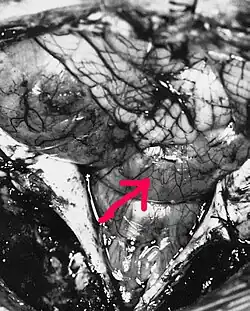

Целью операции является максимальное удаление внутричерепной части опухоли с тем, чтобы у больного не возник неврологический дефицит. Если эпендимома прорастает в дно IV желудочка, что отмечается в 50 % случаев[35], её тотальное удаление становится невозможным. После операции ликвор отправляют на цитологическое исследование с целью определить наличие и количество в нём опухолевых клеток. Доступ к образованиям IV желудочка осуществляется путём срединного субокципитального доступа[3].

Удаление эпендимом спинного мозга производится с применением заднего доступа. После ламинэктомии (удаления задних отделов позвоночника) вскрывается твёрдая мозговая оболочка. Срединный разрез спинного мозга над тканью эпендимомы позволяет её визуализировать. После этого производится по возможности тотальное удаление новообразования[40].